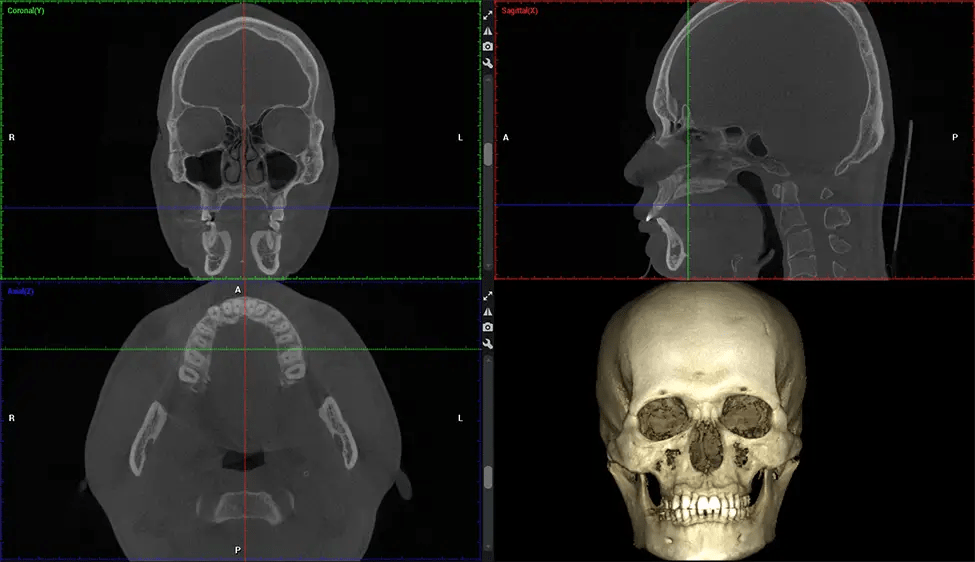

Cone Beam Computed Tomography (CBCT) is an advanced imaging technique used in dentistry and maxillofacial surgery to obtain detailed 3D images of the oral and maxillofacial structures. At Dr G Dental Studio, our CBCT scanners utilize a cone-shaped X-ray beam and a specialized detector to capture images from different angles. A computer then combines these images to create a 3D representation of the patient’s oral anatomy.

This 3D scan, called cone beam computed tomography, gives your dentist a more complete image of your oral anatomy and disease processes than a traditional X-ray. Unlike conventional X-rays, which capture a 2D image of your mouth from various angles, a 3D scan takes multiple digital X-rays for one image. It provides a complete view of your jaw, teeth, nerves, and soft tissues. This enhanced view allows dentists to detect minor issues not visible in traditional 2D scans, such as impacted wisdom teeth or bone fractures in the sinus cavity.

There are many benefits to using CBCT technology, especially compared to the traditional 2D X-ray format. One of the most significant advantages of CBCT scans is that they provide much more information than traditional X-rays. A scan lets your dentist see images from all angles of your jaw and mouth, including your sinuses, nasal cavity, cheekbones, and other surrounding areas. This added information helps your dentist craft a comprehensive treatment plan that addresses all aspects of your oral health.

Another significant benefit is that 3D imaging provides more precise images of your bone structure. These images are more detailed, providing you with a more accurate diagnosis. An accurate diagnosis means better treatment for you.

After the scanning process, the captured X-ray images are processed by the CBCT software, which applies algorithms to reconstruct a detailed 3D image of the scanned area. The software compiles these individual X-ray images and creates a digital 3D representation of the patient’s anatomy. The reconstructed 3D CBCT image can be viewed and analyzed by the dentist or radiologist. This image can be manipulated, rotated, and zoomed in or out to examine specific structures and evaluate the patient’s condition.